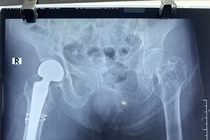

SuperPath là một trong kỹ thuật thay khớp háng tiên tiến nhất hiện nay. Phương pháp này được chỉ định phẫu thuật rộng rãi các bệnh lý khớp háng khác nhau như: hoại tử chỏm xương đùi, thoái hóa khớp háng, gãy cổ xương đùi...

Thay khớp háng nhân tạo ở người cao tuổi luôn là một trong những thách thức đối với kíp gây mê và phẫu thuật viên. Mới đây, khoa Chấn thương chỉnh hình đã thay khớp háng nhân tạo thành công cho cụ bà 107 tuổi.

(khoahocdoisong.vn) - Bệnh viện Chợ Rẫy TPHCM đã phối hợp đa chuyên khoa tiến hành phẫu thuật thay khớp cổ xương đùi thành công cho 1 trường hợp lớn tuổi - bệnh nhân N.T.K. (106 tuổi). Đây là bệnh nhân lớn tuổi nhất được thay khớp cổ xương đùi tại Bệnh viện Chợ Rẫy TPHCM.